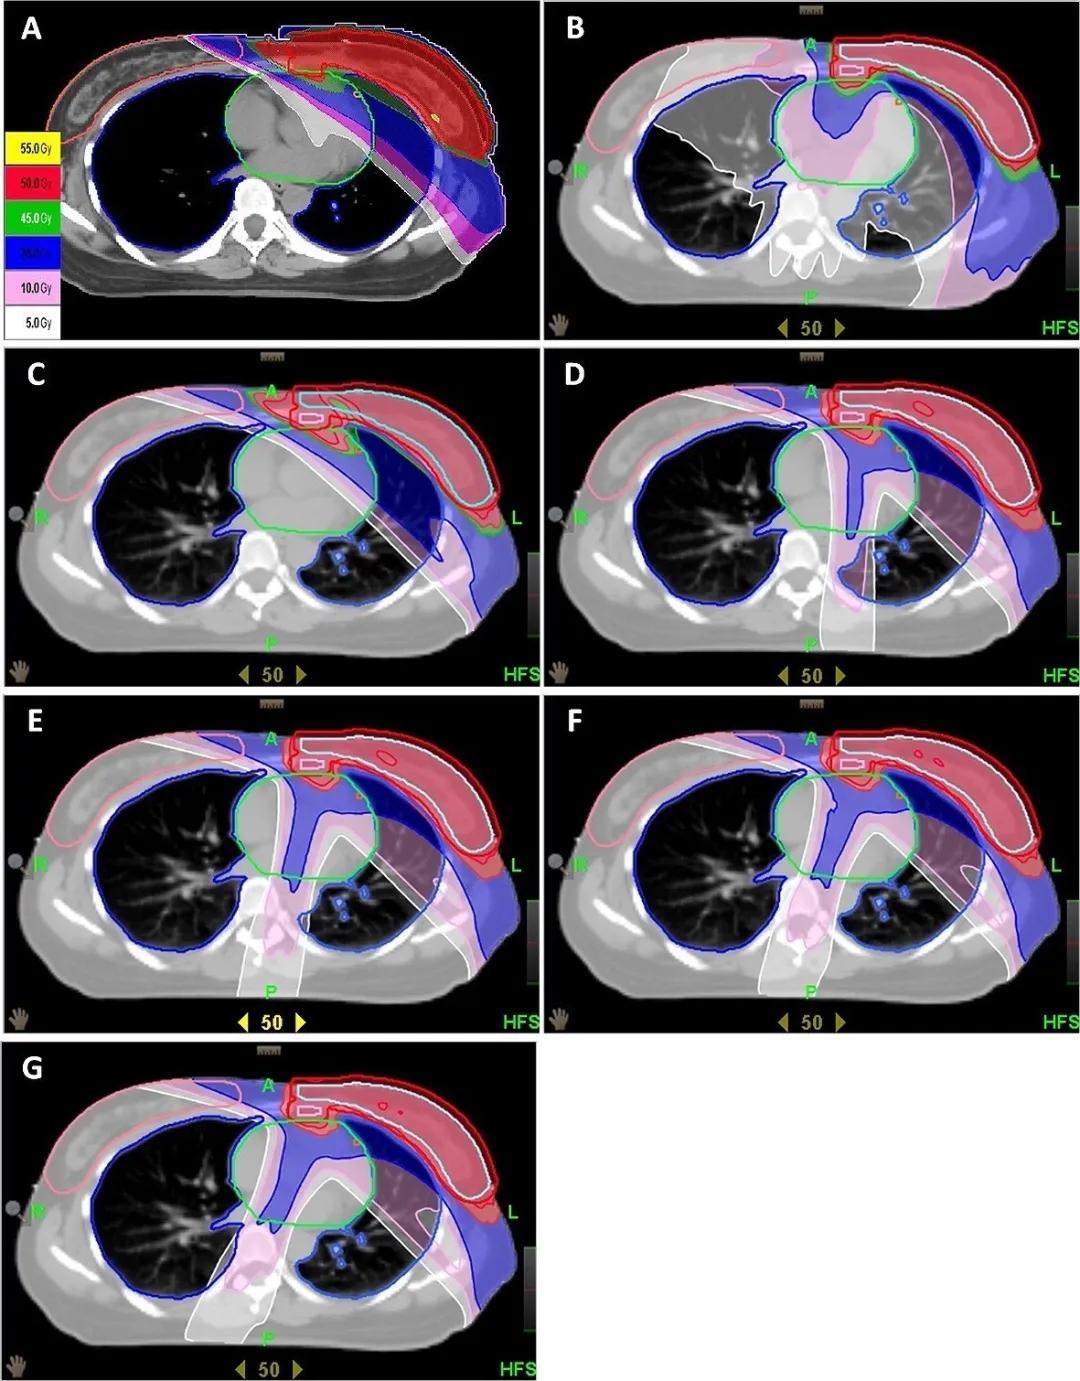

朱教授分享的一项2020年1月份发表在《the British Institute of Radiology》上的研究表明,与调强适形放射治疗(IMRT)相比,托姆刀能够成功降低对心脏、冠状动脉和肺的辐射剂量。

与5F-IMRT(27.0 Gy)平均剂量相比,采用完全定向完全阻滞技术的螺旋层析疗法(CDCB)0、CDCB 10、CDCB 15、CDCB 20和基于器官的定向阻滞(OBDB)技术的左前降支(LAD)平均剂量分别有效降低了31.7%、38.3%、39.6%、42.0%和56.2%。

托姆刀能保护冠状动脉、心肌,可提高早期乳癌生存率,更安全,减少诱发二次癌症风险。